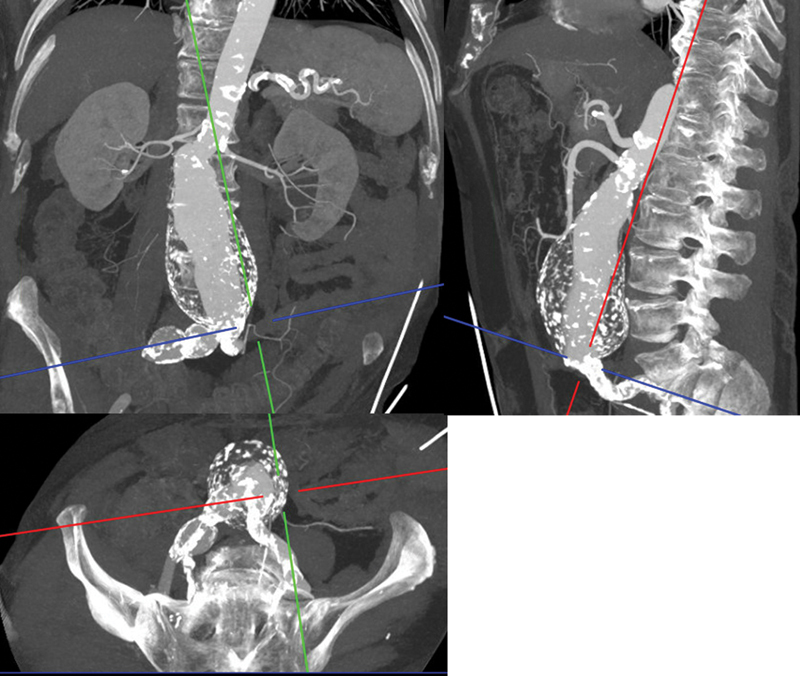

Case description: An 82-year-old male was diagnosed with polyaneurysmal disease. He was treated by femoral, popliteal, and profundal interposition grafts as well as fenestrated endovascular repair (FEVAR) using an Anaconda (Terumo Aortic, Inchinnan, Scotland) endoprosthesis combined with BeGraft peripheral and BeFlared (BF) bridging stent grafts (Bentley InnoMed, Hechingen, Germany).

Conclusion: Polyaneurysmal disease in an aged patient can be treated successfully by thorough case planning, staging of procedures, and combining different vascular surgical techniques. It demonstrates the smooth implantation of the BeFlared in an Anaconda FEVAR.